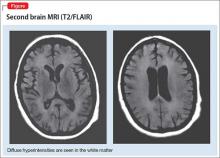

DPHL is a diagnosis of exclusion. A careful history is critical to establish the possibility of a recent anoxic event. MRI findings, including hyperintensities in the cerebral white matter on T2-based sequencing, are suggestive of the disease. A choline peak on magnetic resonance spectroscopy also might be present in patients with DPHL, although it is not spe­cific to the diagnosis.

A second MRI shows diffuse hyperintensities in the white matter that spare the cerebel­lum and brainstem (Figure). This finding is pathognomonic for DPHL.